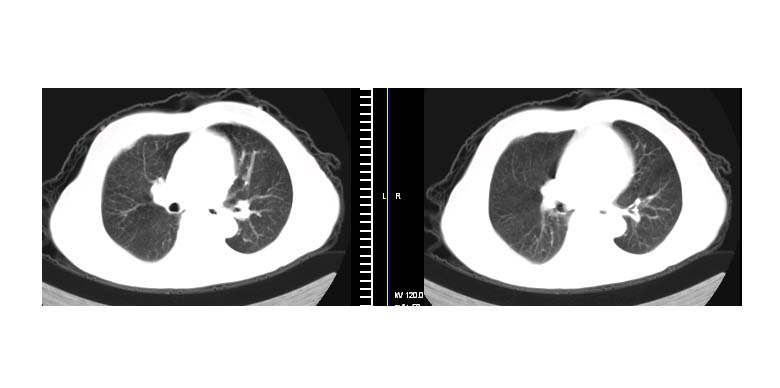

标题: CT11087:男性,82.咳嗽一周.抗炎治疗4-5天效果不明 [打印本页]

标题: CT11087:男性,82.咳嗽一周.抗炎治疗4-5天效果不明

左上肺周围型肺癌伴纵隔淋巴结转移

左肺上叶尖段周围型肺癌伴左肺门淋巴结转移。

左上肺实质性肿块,浅分叶 毛糙 胸膜凹陷征 纵隔淋巴结肿大——支持:左肺上叶周围型肺癌!

左上肺软组织肿块,有分叶,短毛刺,气管旁间隙见有肿大淋巴结,考虑左上周围型肺癌伴纵隔淋巴结转移。

左肺上叶前段肺癌并纵隔淋巴结肿大。